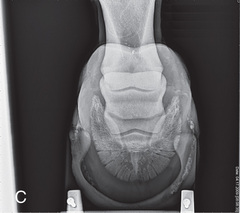

Digit/foot: P-III (distal phalanx, coffin bone) P-II (middle phalanx) P-I (proximal phalanx-pastern) Proximal interphalangeal joint (pastern joint) joint | DP (Standard) (Fig. 24.62B,C) | Dorsal 45-degree proximal–palmarodistal (D45Pr-PaDi) | Foot slightly forward on image receptor. | Perpendicular to foot axis at MSP (midsagittal plane) at area of interest with beam angled ~45 degrees to ground |

| Lateral (Standard) (Fig. 24.62D) | Lateromedial | On a block to elevate limb for P-III; resting on ground for other views. | 90 degrees lateral to MSP, parallel to ground on area of interest: coronary band for PIII | |